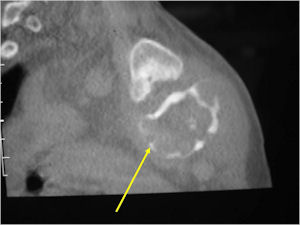

CT Scan:

- More useful for detecting mineralization and evaluating extent of bone destruction than plain X-ray

- The periosteum remains intact around the soft tissue component. Might need a CT scan to detect the subtle calcification (Egg Shell Rim of Calcification) associated with an intact periosteal reaction

- The lesion may be entirely radiolucent but usually shows some degree of mineralization. Mineralization may appear stippled like cartilage but do not see chondroid pathologically. Mineralization is sometimes better detected on a CT scan rather than an x-ray.

- Soft tissue component usually surrounded by shell of reactive bone or periosteum (Egg Shell Rim of Calcification)